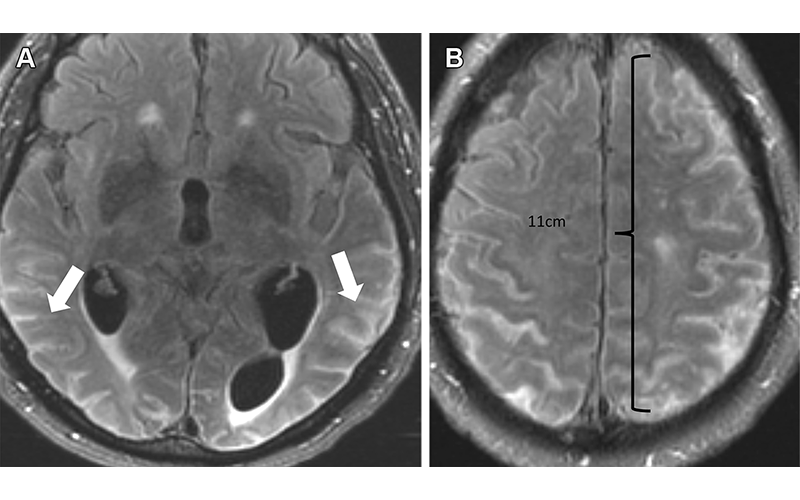

Severe ARIA-E (effusion) in a 76-yearold man with worsening headaches receiving aducanumab therapy for AD. Axial brain MR images from December 2021 (3 weeks after full dose) show multifocal exudates along the sulci with FLAIR hyperintensity (arrows in A), measuring more than 10 cm (severe) with subtle leptomeningeal enhancement (B). Treatment was suspended, and complete resolution of effusion was noted after cessation of therapy.